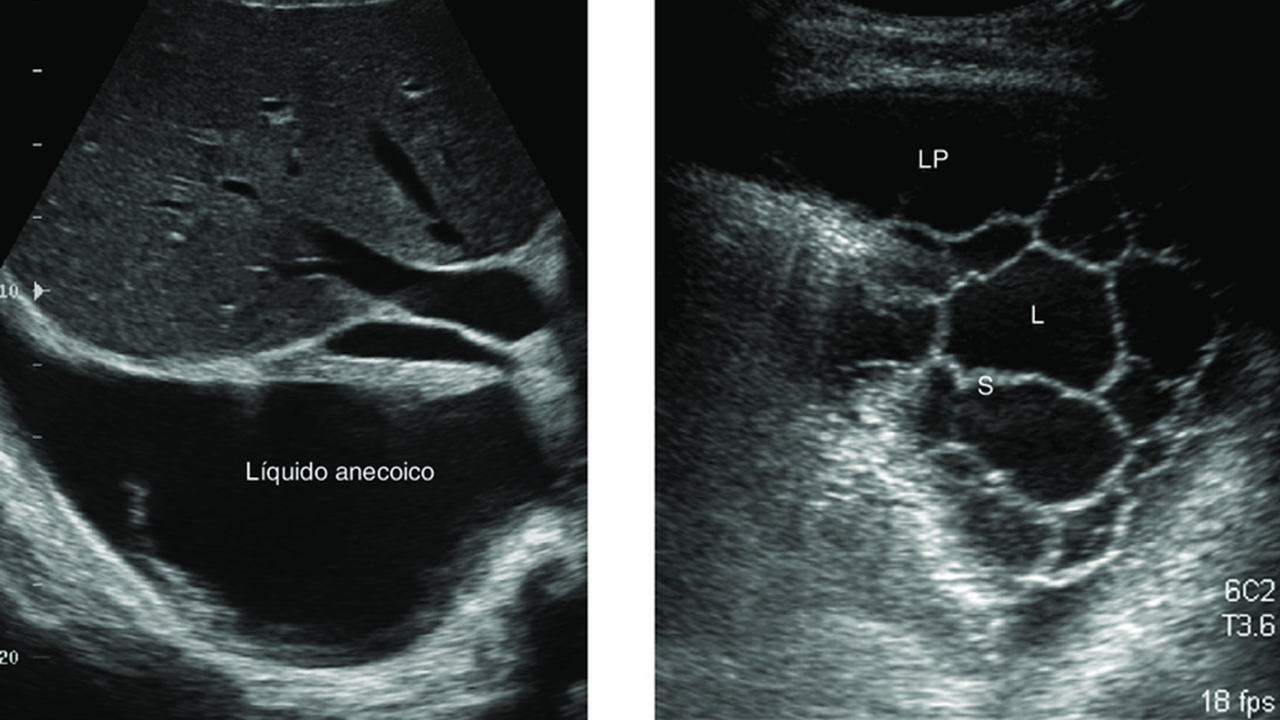

A drenagem de derrame pleural loculado (coleções separadas por septos) é mais complexa que a do derrame livre e geralmente exige intervenção guiada por imagem para garantir a drenagem eficaz. O método preferencial envolve o uso de ultrassonografia (USG) ou tomografia computadorizada (TC) para localizar o ponto exato da loculação, seguido da inserção de um cateter, frequentemente associado ao uso de fibrinolíticos.

Identificação: Realizar USG de tórax para identificar a "bolsa" (loculação) de líquido, garantindo que o local de inserção esteja livre de pulmão ou órgãos adjacentes.

Fibrinolíticos: Em casos de empiema ou derrame parapneumônico complicado com septos, pode ser necessária a injeção intrapleural de fibrinolíticos (como uroquinase ou estreptoquinase) através do dreno para romper as septações e liberar o líquido.